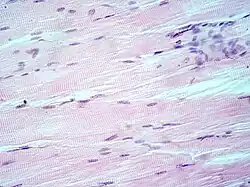

H&E stain

Hematoxylin and eosin stain (or haematoxylin and eosin stain or hematoxylin–eosin stain; often abbreviated as H&E stain or HE stain) is one of the principal tissue stains used in histology.[1][2][3] It is the most widely used stain in medical diagnosis[1] and is often the gold standard.[4] For example, when a pathologist looks at a biopsy of a suspected cancer, the histological section is likely to be stained with H&E.

H&E is the combination of two histological stains: hematoxylin and eosin. The hematoxylin stains cell nuclei a purplish blue, and eosin stains the extracellular matrix and cytoplasm pink, with other structures taking on different shades, hues, and combinations of these colors.[5][6] Hence a pathologist can easily differentiate between the nuclear and cytoplasmic parts of a cell, and additionally, the overall patterns of coloration from the stain show the general layout and distribution of cells and provides a general overview of a tissue sample's structure.[7] Thus, pattern recognition, both by expert humans themselves and by software that aids those experts (in digital pathology), provides histologic information.

Hematoxylin principally colors the nuclei of cells blue or dark-purple,[6][15][14] along with a few other tissues, such as keratohyalin granules and calcified material. Eosin stains the cytoplasm and some other structures including extracellular matrix such as collagen[5][7][14] in up to five shades of pink.[8] The eosinophilic (substances that are stained by eosin)[5] structures are generally composed of intracellular or extracellular proteins. The Lewy bodies and Mallory bodies are examples of eosinophilic structures. Most of the cytoplasm is eosinophilic and is rendered pink.[10][15] Red blood cells are stained intensely red.